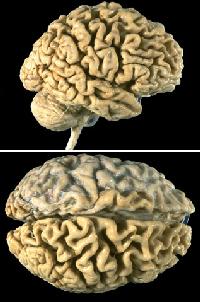

Often times families have questions concerning what Alzheimer's does to the actual brain.

The following photographs will show you.

(These are actual photos of a normal brain and one affected by AD. I'm sorry they are so explicit, but I felt they were important to include.)

Brain Affected by AD

Special Thanks to http://www-medlib.med.utah.edu/WebPath/CNSHTML/CNS013.html for suppling me with these brain images.